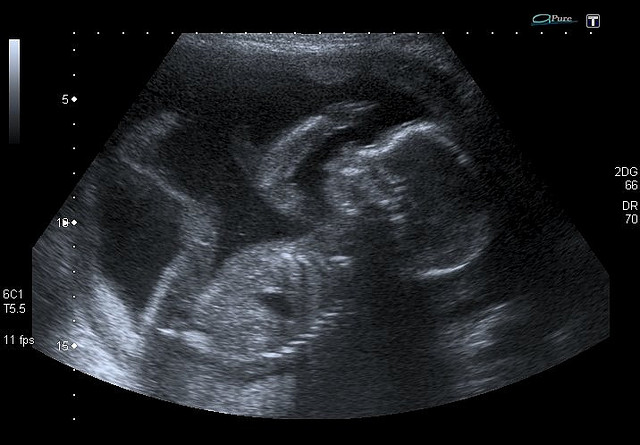

Фото плода на 18-й неделе беременности